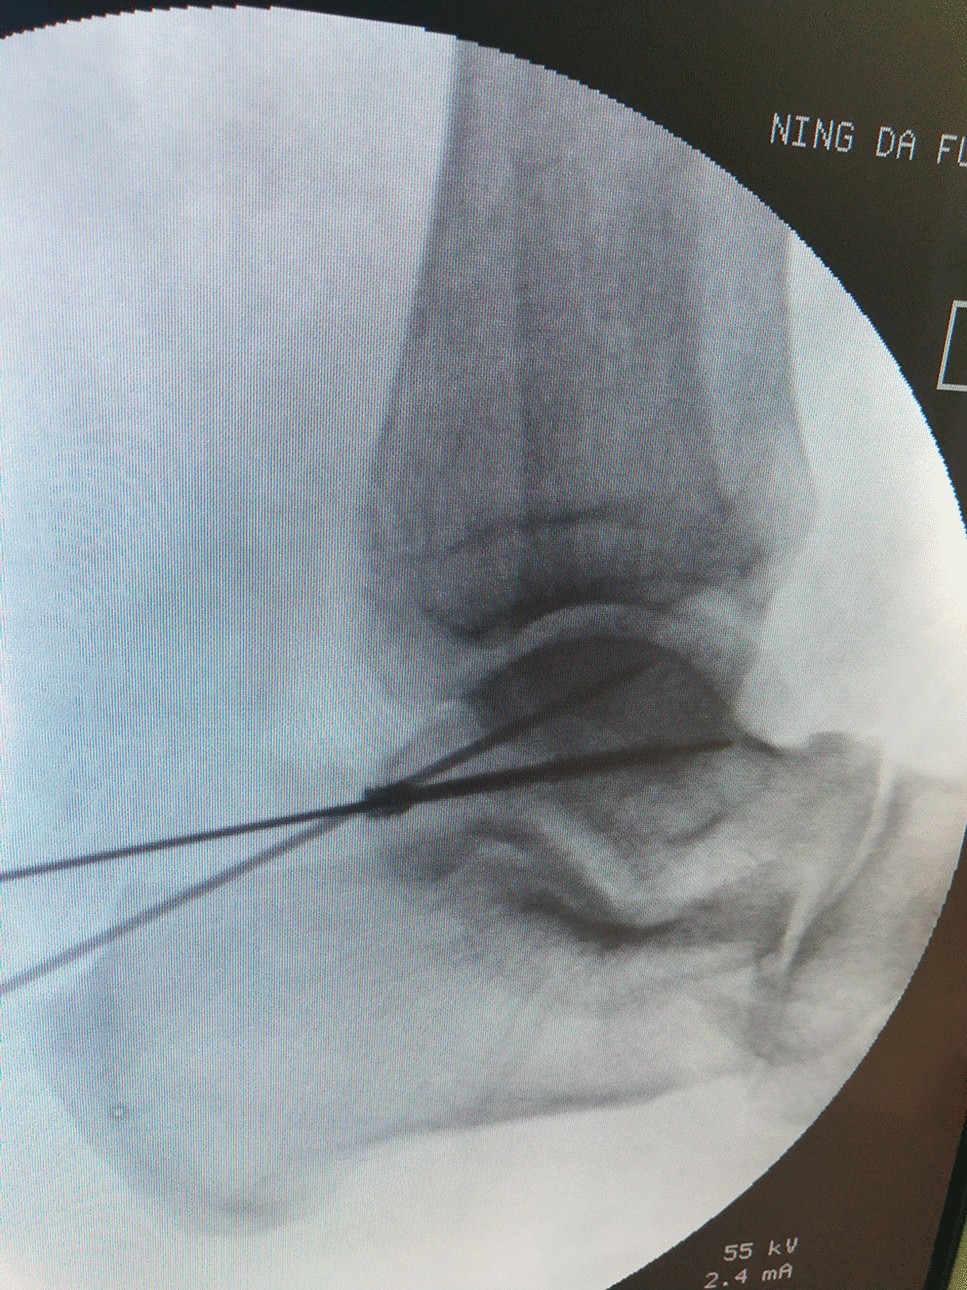

talus fracture

» Talus fracture approach (95) 사진

Talus fracture approach (95) 사진